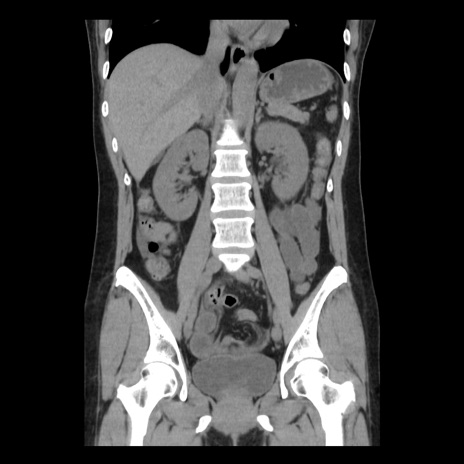

症例10(冠状断像)

【症例】 50歳代女性

【主訴】 腹痛

【現病歴】前日生レバーを食べた。今朝に排便あり。 昼前に突然発症の腹痛を生じ、当院救急外来を受診した。

【既往歴】 子宮筋腫にてで子宮全摘後

【身体所見】 意識清明、腹部:平坦、軟、下腹部やや左を中心に圧痛・反跳痛あり、筋性防御あり

【データ】WBC 7800、CRP 0.07